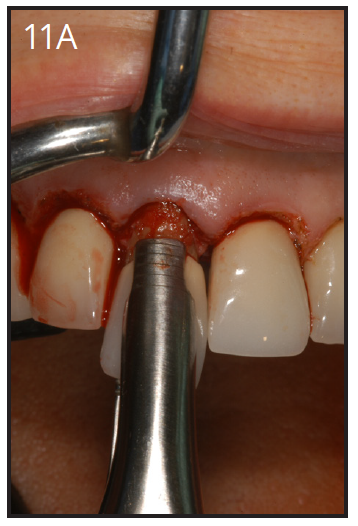

An implant most closely replicates the feel of a natural tooth. Once it is osseointegrated, many patients cannot differentiate an implant from a natural tooth. Furthermore, dental implants do not decay or need a root canal. Even though the cost is slightly more than a bridge, it is a great investment for the future, as implants usually last longer than a bridge. A 10-year report on posterior single implants shows a success rate of 97%.29 Once an implant is placed, an integration/healing time of approximately 4 months is necessary before final crown is placed. A temporary crown can be placed the same day the implant is placed. (Figures 11A-E)

Figure 11A – Extraction of anterior tooth (#8) without detaching the gingiva

Figure 11A